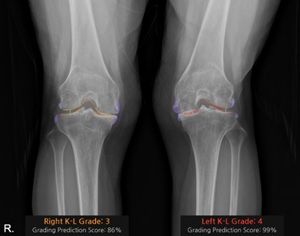

[사진 : 코넥티브 인공지능 관절염 판독 솔루션 '코네보 코아(CONNEVO KOA)'를 적용하여 K-L grade를 판독한 사진. (골극 변형(보라), 관절 간격(3단계 주황, 4단계 빨강)을 시각화 함) K-L grade는 무릎 관절염의 진행 정도를 평가하는 데 사용되며, 단계에 따라 치료 방향이 달라진다]

‘코네보 코아(CONNEVO KOA)’는 무릎 X-ray 영상을 분석해 관절염 심각도를 ‘K-L(Kellgren–Lawrence) 등급’으로 판정하고, 골극과 관절 간격을 시각화해 제공한다.

이를 통해 진단의 일관성을 높이고 환자와 상담 시 유용한 시각자료로 활용할 수 있다.